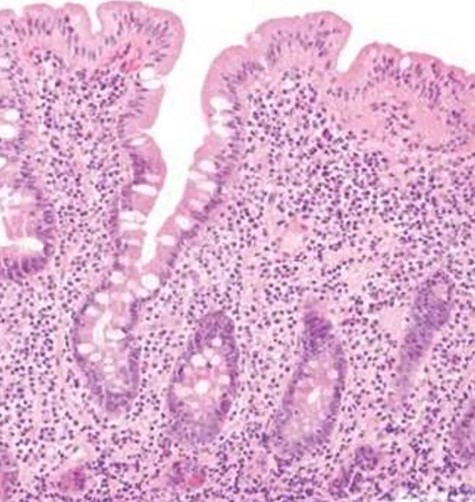

The decision to conduct a colonoscopy was undertaken to exclude inflammatory bowel disease and lower gastrointestinal (GIT) pathology. Colonoscopy revealed several adhesions throughout the pelvic organs (Fig. 1) and a biopsy revealed blunting of villi with subsequent crypt hyperplasia with no crypt abscesses, fistulas or granulomas (Fig. 2). There was a high clinical suspicion of celiac disease and laboratory confirmation was ordered. Lab results: positive immunoglobulin A (IgA) anti-tissue glutaminase 4.6 and immunoglobulin G (IgG) antideamidated gliadin peptide antibodies, IgA tTG 167 U/ml. Laparoscopy was performed as well to exclude any hidden etiologies including gynecological disorders that can lead to the adhesions but was not able to identify the cause.

Biopsy revealed blunting of villi with subsequent crypt hyperplasia with no crypt abscesses, fistulas or granulomas.

Celiac disease is usually diagnosed based on two main pillars: the positivity of the serological tests and the pathological appearance of the intestinal biopsy. Serological testing involves the measurement of IgA anti-TGase—with the exclusion of other malabsorption diseases—which is positive in at least 98% of all cases of celiac disease on a gluten diet [3] as the first line of diagnosis because of its high sensitivity and high negative predictive values compared other non-sensitive tests [4]. IgG anti-gliadin antibodies have the highest sensitivity and specificity (Table 1) [4]. Positive serological testing should mandate duodenal biopsy and histopathological examination as a confirmatory test to ensure that patients are correctly diagnosed with the celiac disease before being subjected to a gluten-free diet for life. The hallmark of the histopathological picture of celiac disease is increased intraepithelial lymphocytes, crypt hyperplasia and villous atrophy (Marsh type 3) [5,6].